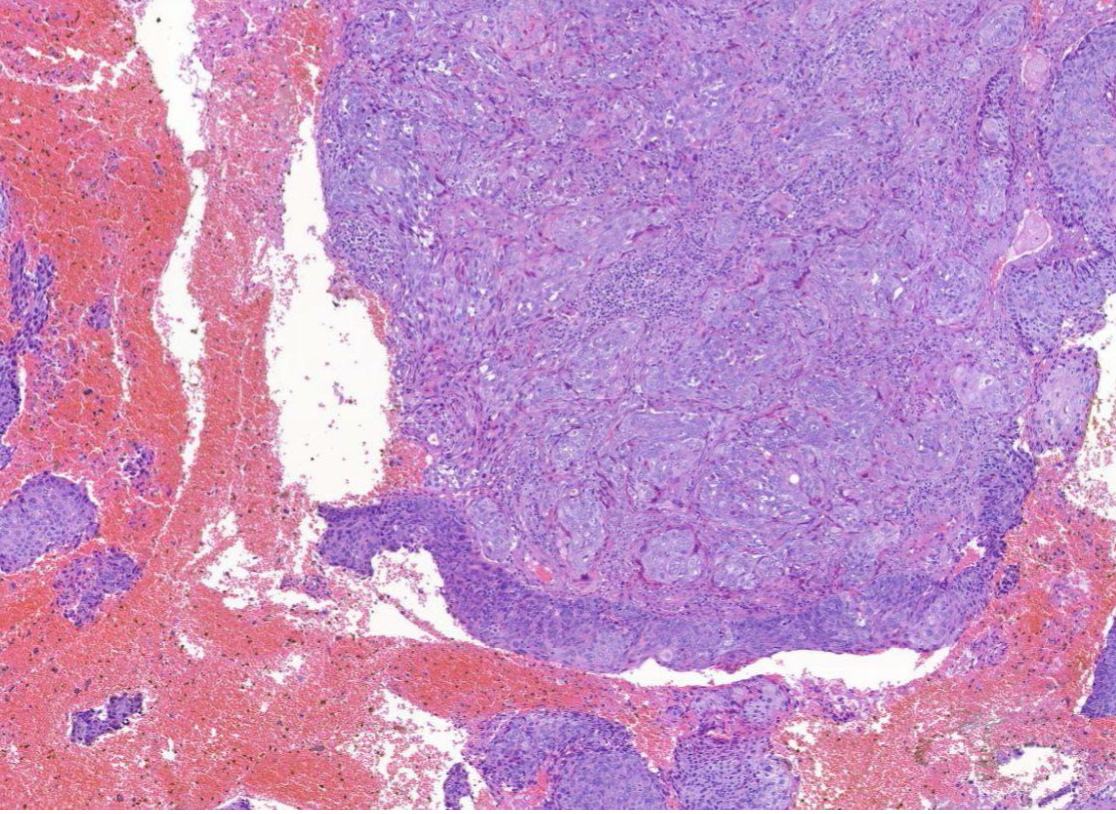

Diagnose?

Duktales Carcinoma in situ

Invasives unspezifisches duktales Mamma-CA